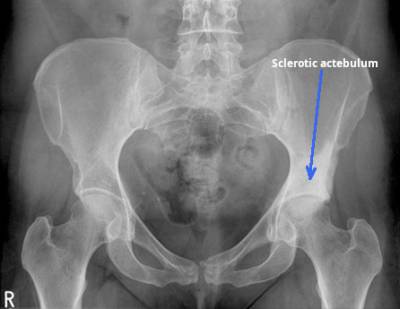

| B | • Bones | • ribs, lumbar vertebrae, sacrum, coccyx, pelvis and proximal femurs |

| C | • Calcification • artifacts | • arterial Ca++, phelobliths, calculi • clips, tubes, implants |